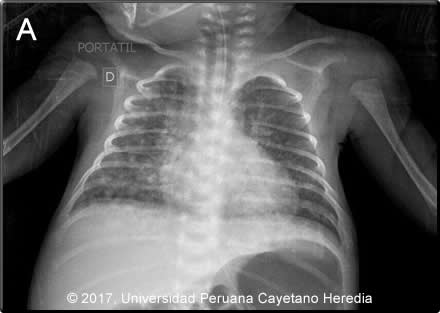

![]() Discussion: On repeat testing, a gastric aspirate from the infant was positive for AFB (3+). Mother and baby were both HIV negative. Investigation of the mother, who remained febrile after the curettage, included chest X-ray and CT (Image B, C) showing a diffuse micronodular pattern. A pelvic CT (not shown) showed a large heterogeneous uterus which on examination after hysterectomy with bilateral salpingectomy, showed a chronic granulomatous process with giant multinucleated cells in the endometrium, myometrium (Image D) and Fallopian tubes (Image E). In addition, vascular emboli of tissue with granulomatous reaction in the parametrium (Image F) were seen though Ziehl-Neelsen stain was negative. The mother remained febrile after surgery. The diagnosis of miliary tuberculosis in the mother with genital involvement and the finding of AFB in the child led to the diagnosis of congenital tuberculosis and the need to start antituberculous therapy (RIPE) in both. Congenital tuberculosis is the perinatal transmission of M. tuberculosis. It is thought to be acquired in any of the following ways: transplacentally, where the primary complex is found in the liver; by aspiration of infected amniotic fluid during birth, with the lungs as the primary focus, or ingestion of infected amniotic fluid, where the primary infection site is in the gut. [N Engl J Med. 1994; 330:1051–4]. The differential diagnosis in a newborn presenting with this clinical syndrome should include neonatal sepsis, toxoplasmosis, rubella, CMV, HSV (TORCH) , other congenital infections consider within the TORCH complex as others (O) including Syphilis, Parvovirus B19, VZV; HIV. In preterm newborn with respiratory distress consider hyaline membrane syndrome (respiratory distress syndrome). The Cantwell criteria for congenital TB are: Although in our case, there was no evidence of a liver primary complex on ultrasound, the presence of genital tuberculosis in the mother supports also transplacental acquisition of MTB. The diagnosis of tuberculosis in an infant is based on a TST result, which is often negative, and a chest radiograph or other radiologic studies in a patient with a compatible clinical syndrome. Microbiological confirmation should be made whenever possible by examining specimens such as gastric aspirate, ascitic fluid, endotracheal aspirate, middle ear fluid, and CSF [Pediatrics 1980;66:9804]. |